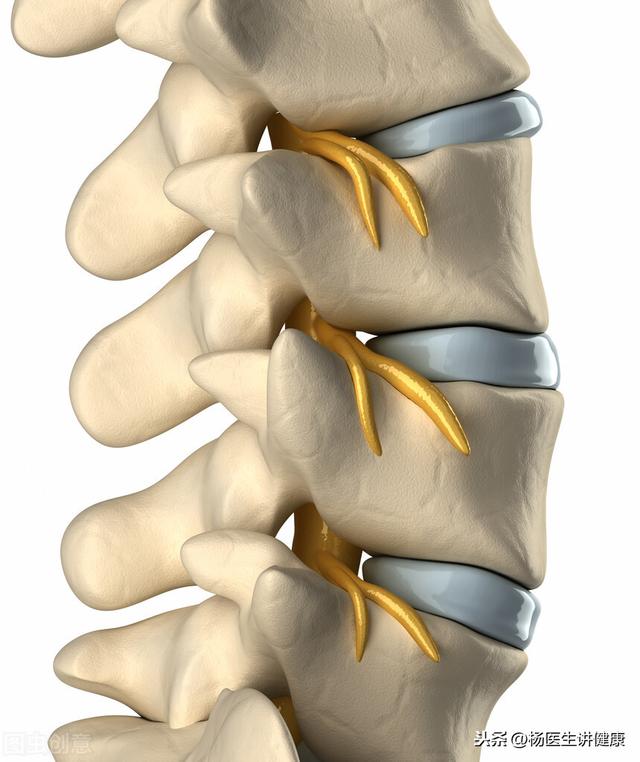

Un disque intervertébral est le tissu situé entre les vertèbres et les vertèbres. Entre les vertèbres et les vertèbres se trouvent l'anneau fibreux et le noyau pulpeux, qui entoure le noyau pulpeux et est fixé entre les vertèbres comme un sandwich.

Une hernie discale se produit lorsque l'anneau fibreux se rompt et que le noyau pulpeux à l'intérieur sort et fait saillie vers l'arrière, comprimant la moelle épinière ou les racines nerveuses, provoquant ainsi des symptômes tels que la douleur et la paralysie.

Une hernie discale est un état irréversible dans lequel un disque intervertébral est constitué d'un anneau fibreux enveloppant le nucleus pulposus, qui peut être imaginé comme un pain de mie, le pain étant l'anneau fibreux et le sandwich étant le nucleus pulposus gélatineux. L'anneau fibreux est une structure cartilagineuse qui, en plus d'entourer le noyau pulpeux et de l'isoler du corps, a également pour fonction de fournir un certain degré d'élasticité et de soutien afin de former une unité fonctionnelle pour les mouvements complexes de la colonne vertébrale humaine. Une véritable hernie discale est une saillie du noyau pulpeux causée par une rupture de l'anneau fibreux. Le nucleus pulposus a deux caractéristiques principales : premièrement, il contient beaucoup d'eau et le mouvement de la colonne vertébrale est causé par le mouvement du corps à travers le mouvement de l'eau en pressant le nucleus pulposus qui ressemble à de la pâte. Deuxièmement, le nucleus pulposus est l'un des trois principaux auto-antigènes de l'organisme, ce qui est la cause principale de la douleur d'irritation nerveuse après une hernie discale. Les auto-antigènes sont des acides forts, des bases et d'autres produits chimiques très irritants et corrosifs pour l'organisme. Pourquoi y a-t-il une hernie discale ? Une mauvaise posture pendant longtemps a provoqué la déviation du noyau pulpeux, une pression longtemps inégale dans le disque, et finalement la rupture de l'anneau fibreux est une cause, la violence a provoqué la rupture de l'anneau fibreux et la rupture du noyau pulpeux est également une cause, mais la première cause est plus fréquente dans la clinique. Les disques intervertébraux présentent une dégénérescence, un bombement et une protrusion en fonction du degré d'endommagement de l'anneau fibreux. Lorsque le nucleus pulposus s'écoule complètement, on parle de prolapsus, et le nucleus pulposus prolapsé se promène dans le canal rachidien, ce qui constitue une situation plus dangereuse. Selon les caractéristiques du noyau pulpeux, qui contient beaucoup d'eau, le stade initial de la hernie discale peut être traité de manière conservatrice pour obtenir de bons résultats, car l'eau contenue dans le noyau pulpeux est absorbée et il y a un froissement morphologique, et les symptômes naturels sont soulagés lorsqu'ils ne provoquent pas d'irritation des nerfs. La nature chimique du noyau pulpeux facilite également la calcification éventuelle du noyau pulpeux. Et en raison de la nature corrosive du nucleus pulposus, lorsqu'il fait saillie dans une brèche, celle-ci ne fera que s'agrandir, ne parvenant pas à cicatriser et provoquant finalement un cercle vicieux de saillie. Le traitement conservateur implique généralement le repos au lit pendant la période de poussée et l'application d'analgésiques anti-inflammatoires, de relaxants musculaires, d'hormones, etc. pour soulager les symptômes. Pour clarifier quelques points : 1, les médicaments chinois exclusifs, la médecine chinoise n'a pas de description pharmacologique claire, il n'est pas recommandé d'augmenter la charge sur le foie et les reins ; 2, le soutien lombaire n'est pas recommandé parce que le soutien lombaire rendra le muscle lombaire atrophié, ce qui aggravera les symptômes des vertèbres lombaires encore plus. Pour connaître une petite hernie discale lombaire, il faut d'abord connaître les symptômes de la douleur aux jambes principalement, une simple douleur au dos n'est certainement pas une hernie discale ; 3, tous les massages, la thérapie sacrée, l'injection intravertébrale et même un petit couteau à aiguille sont dommageables pour la maladie et ne sont pas recommandés pour le traitement. Le Tui na peut aggraver la hernie, la thérapie sacrée, les injections intra-durales provoquent des adhérences locales, qui peuvent aggraver les symptômes ou gêner l'intervention chirurgicale ultérieure. L'efficacité des petites aiguilles est encore plus incertaine, pour de nombreuses raisons qui ne sont pas bien connues des non-initiés. Bien entendu, la physiothérapie, les massages, l'acupuncture et d'autres méthodes visant à soulager la tension musculaire peuvent toujours être utilisées. Enfin, en ce qui concerne la chirurgie, les symptômes neurologiques ne sont toujours pas soulagés, ou l'apparition d'un impact urinaire et fécal, d'orteils du pouce, d'un trouble de l'extension dorsale de la cheville et d'autres symptômes du syndrome de la cauda equina doivent faire l'objet d'un traitement chirurgical ; en cas d'instabilité de la colonne lombaire et d'autres maladies, un traitement chirurgical doit être envisagé ; il est recommandé d'écouter l'avis des spécialistes sur la méthode chirurgicale spécifique, mais la chirurgie de la hernie discale lombaire, quel que soit le type d'intervention, est une réparation, plutôt qu'une réparation. Il s'agit là d'une différence fondamentale.

Il est difficile à récupérer ! Cela est dû à sa structure. Le disque lombaire n'est pas un tout, il se compose d'un noyau pulpeux interne et d'un anneau fibreux externe, derrière lesquels se trouvent des ligaments. Par conséquent, une hernie discale n'est pas une hernie du disque dans son ensemble, mais une "extrusion" progressive du nucleus pulposus du disque. Au stade initial, l'anneau fibreux entourant le nucleus pulposus n'est pas détruit, ce qui peut être appelé "bombement" du disque intervertébral lombaire. Au stade final, lorsque le nucleus pulposus traverse l'anneau fibreux qui l'entoure, voire pénètre dans le canal rachidien et exerce une pression sur les nerfs, il s'agit d'une "hernie" du disque intervertébral lombaire. Par conséquent, si une hernie discale lombaire se produit, cela signifie que la structure de l'anneau fibreux entourant le disque lombaire a été détruite, comme dans le cas d'une "hernie", et que le nucleus pulposus hernié a beaucoup de mal à revenir. En outre, l'anneau fibreux qui entoure le nucleus pulposus a non seulement une mauvaise circulation sanguine, mais aussi une mauvaise cicatrisation, de sorte que même si le nucleus pulposus se rétablit à peine, il fera facilement à nouveau hernie.